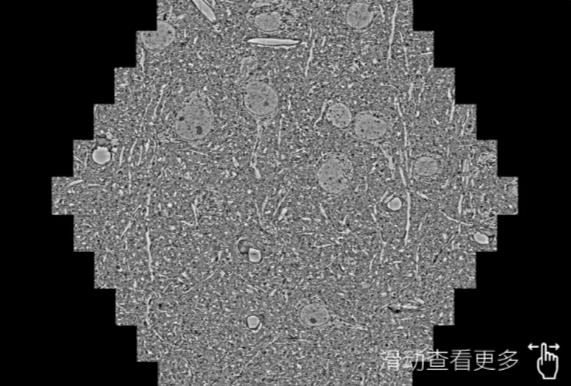

鼠脑切片。左图使用金华蔡司金华扫描电镜MultiSEM706对165μmx143pm面积区域成像,耗时仅需1.5秒。右图为鼠脑切片中30μm区域放大效果。样品由芝加哥大学B.Kasthuri提供。

使用蔡司高速金华扫描电镜MultiSEM对1mm²人脑皮层组织进行高分辨成像,并对其中的各种细胞结构进行三维重构分析。左图展示了2x3mm²组织平面中锥体神经元的三维重构效果。右图显示了局部体积神经元三维重构。图像由哈佛大学chtman实验室提供,渲染图由D. Berger 制作。